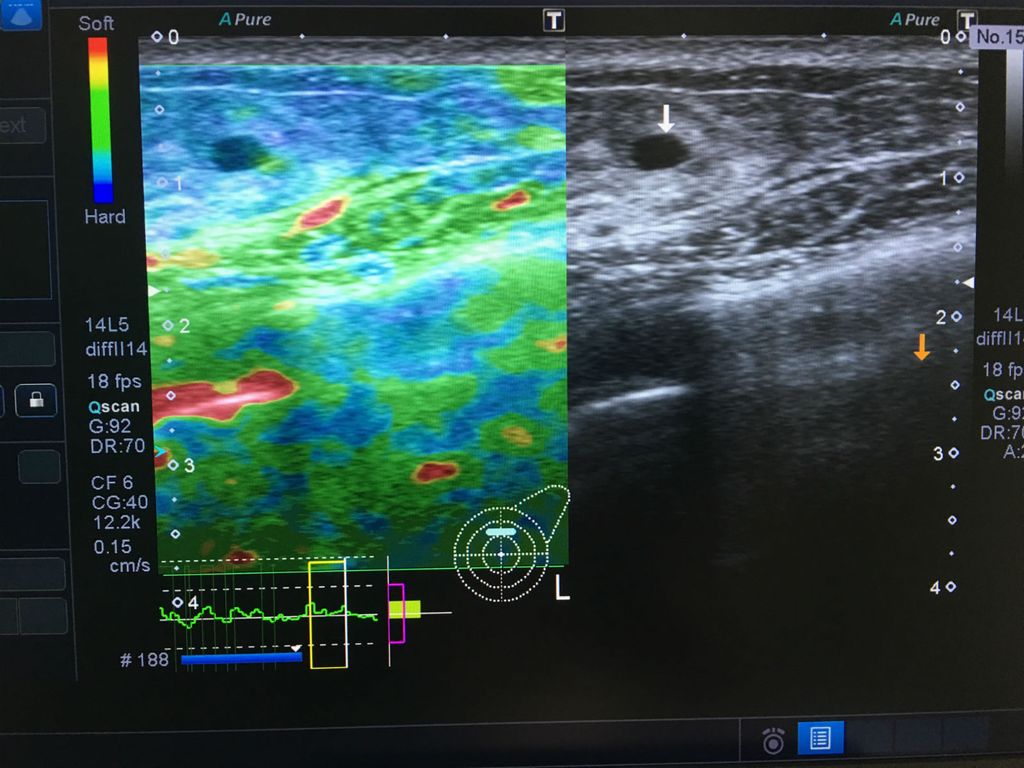

Kolor dopler ultrazvukom najviše klase, koji danas ima i posebne sofverske programe kao što je elastografija (SE) strain ili SWE – share wave elastografija, može se određivanjem čvrstoće tkiva dosta pouzdano, bez punkcije ili biopsije, utvrditi je li žarišna promjena koja odgovara fibroadenomu zloćudna ili dobroćudna.

Princip kvalitativne (SE) elastografije temelji se na činjenici da je fibroadenom zbog svoje gumaste strukture stlačiv, stoga je moguća njegova blaga deformacija pritiskom sonde, a princip SWE elastografije kvantitativno je mjerenje (5-10 uzoraka mjerenja) čvrstoće tkiva, kojim je moguće novim ultrazvučnim uređajima određivati čvrstoću tkiva u kPa ili mjeriti brzinu prolaska ultrazvučnih valova kroz žarišnu promjenu (FA).

Prema standardiziranim mjerenjima koje je donijelo Europsko i svjetsko društvo za ultrazvuk u medicini i biologiji, zaključujemo je li uočena promjena u dojci fibroadenom ili je došlo do promjene već ranije utvrđenog fibroadenom, odnosno je li karcinom dojke.